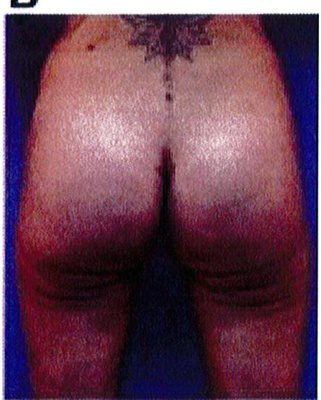

Hình. 18.. (A) Hình anh trước và (B) và sau phẫu thuật làm đầy mông của bệnh nhân được đặt khối implant dưới cân thể tích 225 mL, hai bên.

Bệnh nhân 31 tuổi tiền sử khỏe mạnh, có chỉ định nâng mông bằng implant do thiếu hụt thể tích. Hai khối anatomic implant 225 mL polyurethane dạng gel được đặt ở vị trí dưới cân. Sau phẫu thuật không ghi nhận biến chứng trong suốt quá trình hồi phục, vết mổ liền tốt (Hình 18).